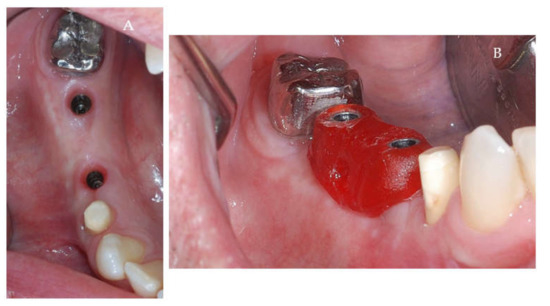

Clinical and CBCT aspects of patient from the test group, describing the stages of S-GBR technique and implant-prosthetic stage, are presented in Figure 1, Figure 2, Figure 3, Figure 4, Figure 5, Figure 6, Figure 7, Figure 8, Figure 9, Figure 10 and Figure 11. CBCT exam allows the evaluation of the horizontal alveolar bone defect and the position of the mandibular alveolar nerf (Figure 1A,B). Figure 1C,D show cross-sectional CBCT aspects of the implant sites. Figure 2 shows the narrowed mandibular alveolar bone with horizontal resorption. Figure 3 shows the exposed buccal surface of the alveolar ridge with severe horizontal resorption, after flap opening. The inserted implants (4.5 mm diameter, 11.5 mm length) and osteosynthesis screws (45° from the occlusal plan) are shown in Figure 4A. The placement of graft (autologous bone and xenograft) and collagen membrane is shown in Figure 4B. Figure 5A shows tension-free sutures, due to periosteal incisions alveolar ridge. Figure 5B shows clinical aspect at 7 months after surgery, with gingival tissue adherent on the reconstructed alveolar ridge. Figure 6 shows OPG aspect at follow-up of 7 months, with osseointegration of the dental implants. Figure 7A shows clinical aspect before osteosynthesis screws removal. Figure 7B shows clinical aspect after osteosynthesis screws removal. Figure 8A shows healthy peri-implant soft tissues. Figure 8B shows repositioning key for perfect position of abutments. Figure 10A,B show clinical aspects of implant-supported prosthetic restoration. Figure 11A,B show CBCT aspects of Osseo integrated dental implants at 24 months follow-up.

Figure 8.

(A,B) Clinical aspects at the second stage surgical session. (A) Aspect before screw removal. (B) Aspect after screw removal.